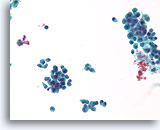

Lobulair carcinoom

Lobulair carcinoom, Borst FNA, celblok.

Lobulaire carcinoomcellen lijken in het stromaweefsel te zijn ingebed, zodat de indruk wordt gewekt van hypercellulariteit. Dit kan de reden zijn waarom cytologische preparaten van een lobulair carcinoom vaak weinig maligne cellen tonen.

20X

Lobulair carcinoom, Borst FNA, celblok.

Lobulaire carcinoomcellen lijken in het stromaweefsel te zijn ingebed, zodat de indruk wordt gewekt van hypercellulariteit. Dit kan de reden zijn waarom cytologische preparaten van een lobulair carcinoom vaak weinig maligne cellen tonen.

20X

Lobulair carcinoom, Borst FNA, celblok.

Een enkele rij minimaal atypische spaarzame cellen die op en in de stromale fragmenten vastzitten, kan worden waargenomen. Let op de kenmerkende targetoïde intracytoplasmische vacuolen van lobulaire neoplasie.

40X

Lobulair carcinoom, Borst FNA, celblok.

Een enkele rij minimaal atypische spaarzame cellen die op en in de stromale fragmenten vastzitten, kan worden waargenomen. Let op de kenmerkende targetoïde intracytoplasmische vacuolen van lobulaire neoplasie.

40X